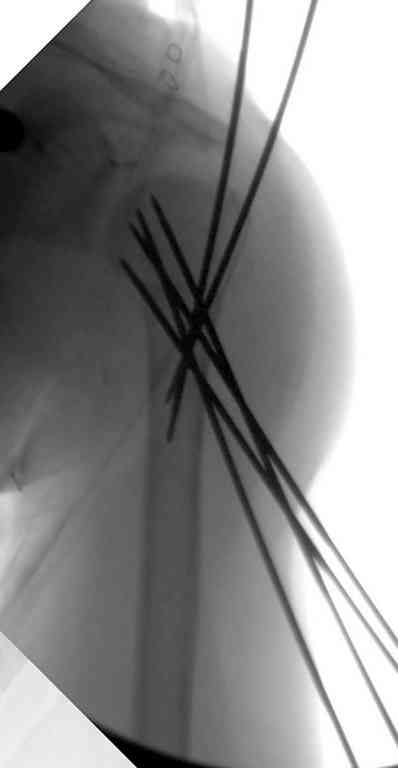

Сделали напряженными спицами по методике А.Ф.Лазарева со товарищи Репозиция сделана спицевым дистрактором, проксимальная спица была проведена в полскости деформации перпендикулярно оси наклонившейся головки. Получилось все довольно легко. Спицы малость покороче можно было сделать, ну да удалять потом легче будет.

Картинка в приложении.

Очень даже неплохо получилось. Молодцы! Лучше чем на 3D "репозиции".

В приложении. Схема простая - по спице в каждый отломок, полукольцо проксимально, кольцо дистально, два телескопа. Как уже писал, ключевым моментом было введение спицы в плоскости диформации проксимального

оттдела плеча.